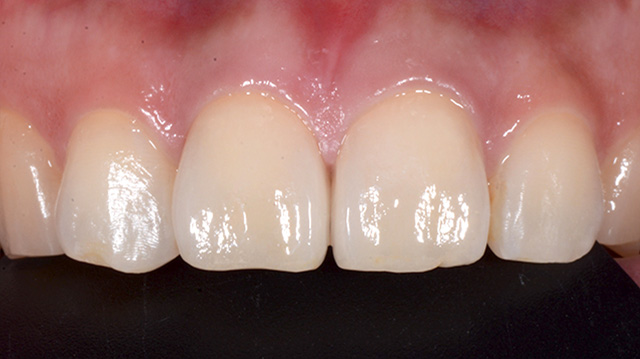

| 年代・性別 | 40代 男性 |

|---|---|

| 主訴 | 前歯の色が気になる |

| 治療回数 | 3回 |

| 治療期間 | 約1ヶ月 |

| 費用 | 仮歯 5,500円 ジルコニアクラウン 176,000円 |